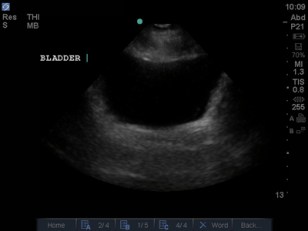

- Focussed Assessment Sonography in Trauma (FAST) Ultrasound